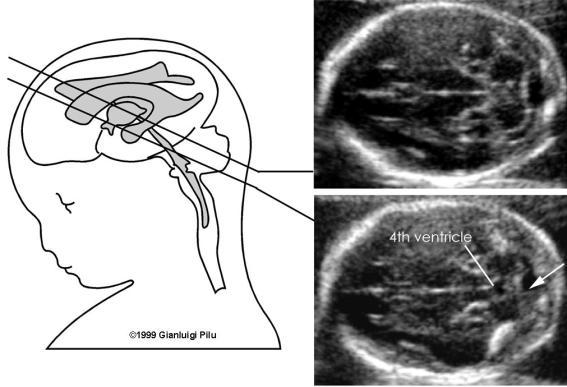

What plane are brain anatomy and measurements taken in?

transverse

What images are taken of the fetal head?

Faux cerebri (IHF)

Choroid Plexus

cavum septum pellucidum

Thalami

Cerebral peduncles

cerbellum & cisterna magna

What is the function of the cerebellum?

equilibrium

What is the measurement of the cisterna magna at 20 weeks?

10 mm or less

What are the parts of the cerebellum?

vermis and 2 lobes

Why is the cerebellum measured?

good correlation with GA

excluding Arnold Chiari seen in spina bifida

Dandy Walker syndrome

What is Arnold Chiari?

downward displacement of the cerebellum through the foramen magnum

banana shaped cerebellum

What is Dandy Walker?

hypoplasia of the vermis and cephalad rotation of the vermian

remnant cystic dilatation of the fourth ventricle extending

posteriorly